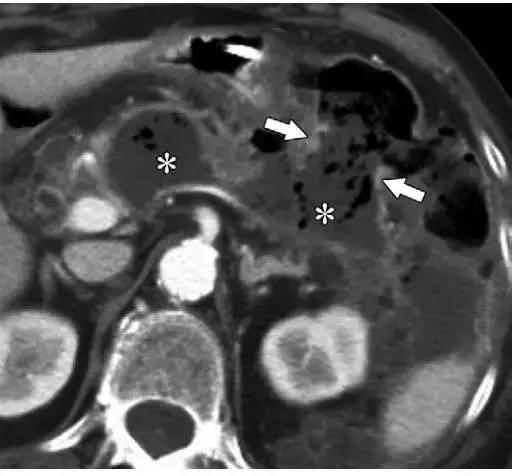

任何病变都可以是无菌的也可以是受感染的,但在坏死物中感染的发生率较高。临床上,病情稳定的患者出现代谢失调的表现应该考虑感染可能,在影像学上表现为:病灶中出现气体。

感染所产生的气体多表现为病灶内弥漫多发的小气泡(图 8,12)。

如果坏死物侵袭肠管,致使出现胰肠管瘘,感染的内容物里的气体也可来自肠道,多见于结肠和十二指肠(图 13)。

图 12 37 岁女性坏死性胰腺炎患者。a 发病 3 周轴位增强 CT 示胰尾(*)和胰周 ANC 含有脂滴(箭头)。b 发病 6 周患者因呼吸困难再次入院,轴位增强 CT 图像可见新发少量气体影,提示 WON 感染

图 13 74 岁女性坏死性胰腺炎患者。发病 5 周增强轴位 CT 可见多发气体影(*)。可见横结肠远端与病变形成瘘管,含有气体和液体(箭头),可以解释 WON 含有气体的原因